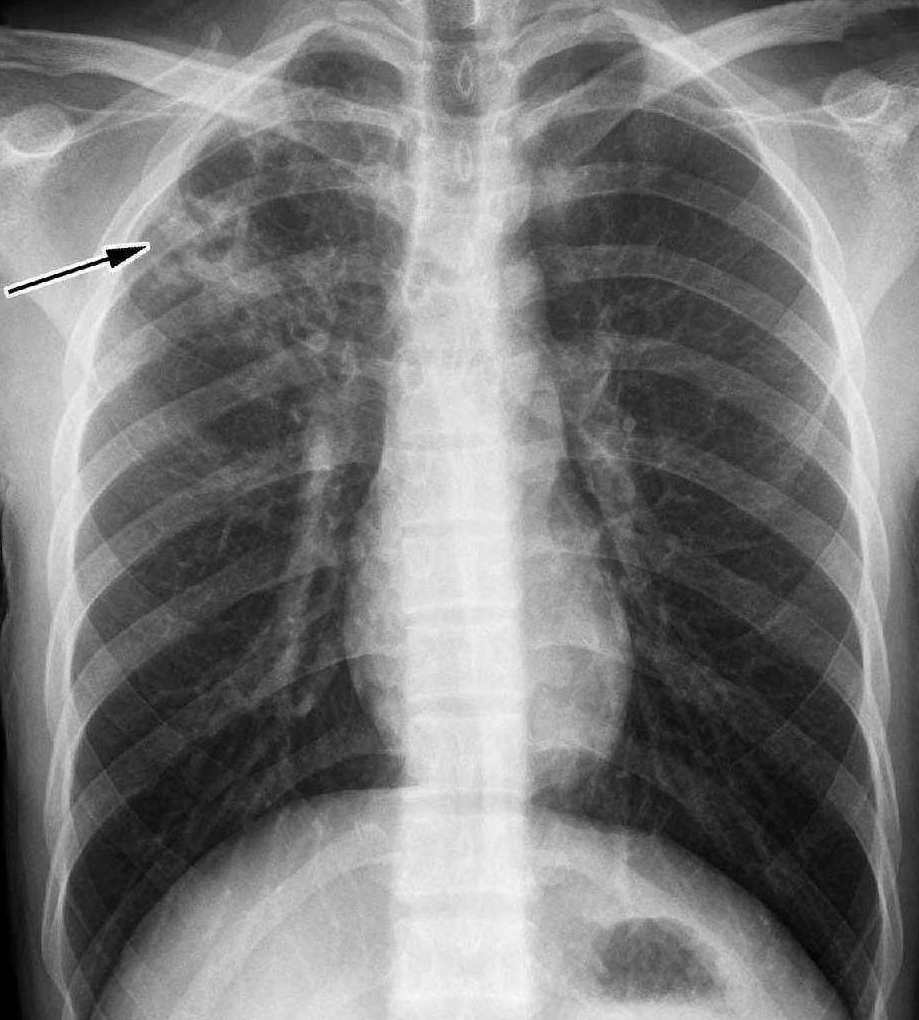

高微微肺结核概述:介绍一位患有肺结核的女性患者,强调其病情严重和需要关注与治疗的必要性

高微微 肺结核